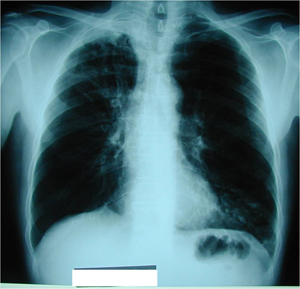

Εικόνα 1

Οπισθιο-πρόσθια ακτινογραφία θώρακος. Πυκνοατελεκτασία με φλεγμονώδη στοιχεία στον δεξιό άνω λοβό. Η βρογχοσκόπηση έδειξε ότι υπήρχε όγκος στο στόμιο του λοβαίου βρόγχου του άνω λοβού που το απέφρασσε πλήρως. Η βιοψία έδειξε ότι πρόκειται για πλακώδες καρκίνωμα πνεύμονος.